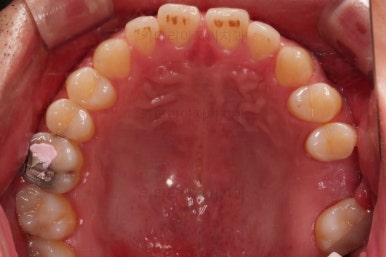

초진 시의 입안 모습입니다.

어금니가 빠져서 결손치아가 있고 치아 사이에 틈새도 있어서 교정치료도 함께 원한다고 내원해 주셨어요.

사진에서 보시는 바와 같이 윗니 1개, 아랫니 1개의 결손 부위가 보입니다.

윗니 어금니 중에는 신경치료를 마무리 못하고 임시재료로 메꿔뒀던 부위도 보이고요.